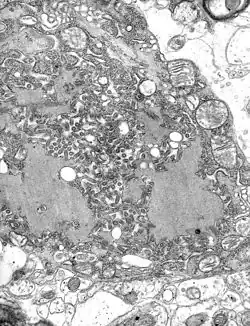

Zdjęcie z mikroskopu elektronowego komórki zarażonej wirusem wścieklizny: widać liczne wiriony wirusa (szare, pałeczkowate struktury) i większe, ciemniejsze ciałka wtrętowe Negriego

Ciałka Negriego (ang. Negri bodies) – okrągławe, podobne do erytrocytów ciałka wtrętowe spotykane w cytoplazmie neuronów okolicy hipokampa i komórek Purkiniego móżdżku, patognomoniczne dla wścieklizny[1]. Immunohistochemicznie i ultrastrukturalnie można w nich wykazać obecność wirusa wścieklizny. Nazwa ciałek pochodzi od ich odkrywcy, włoskiego lekarza, patologa i mikrobiologa Adelchi Negriego[2].